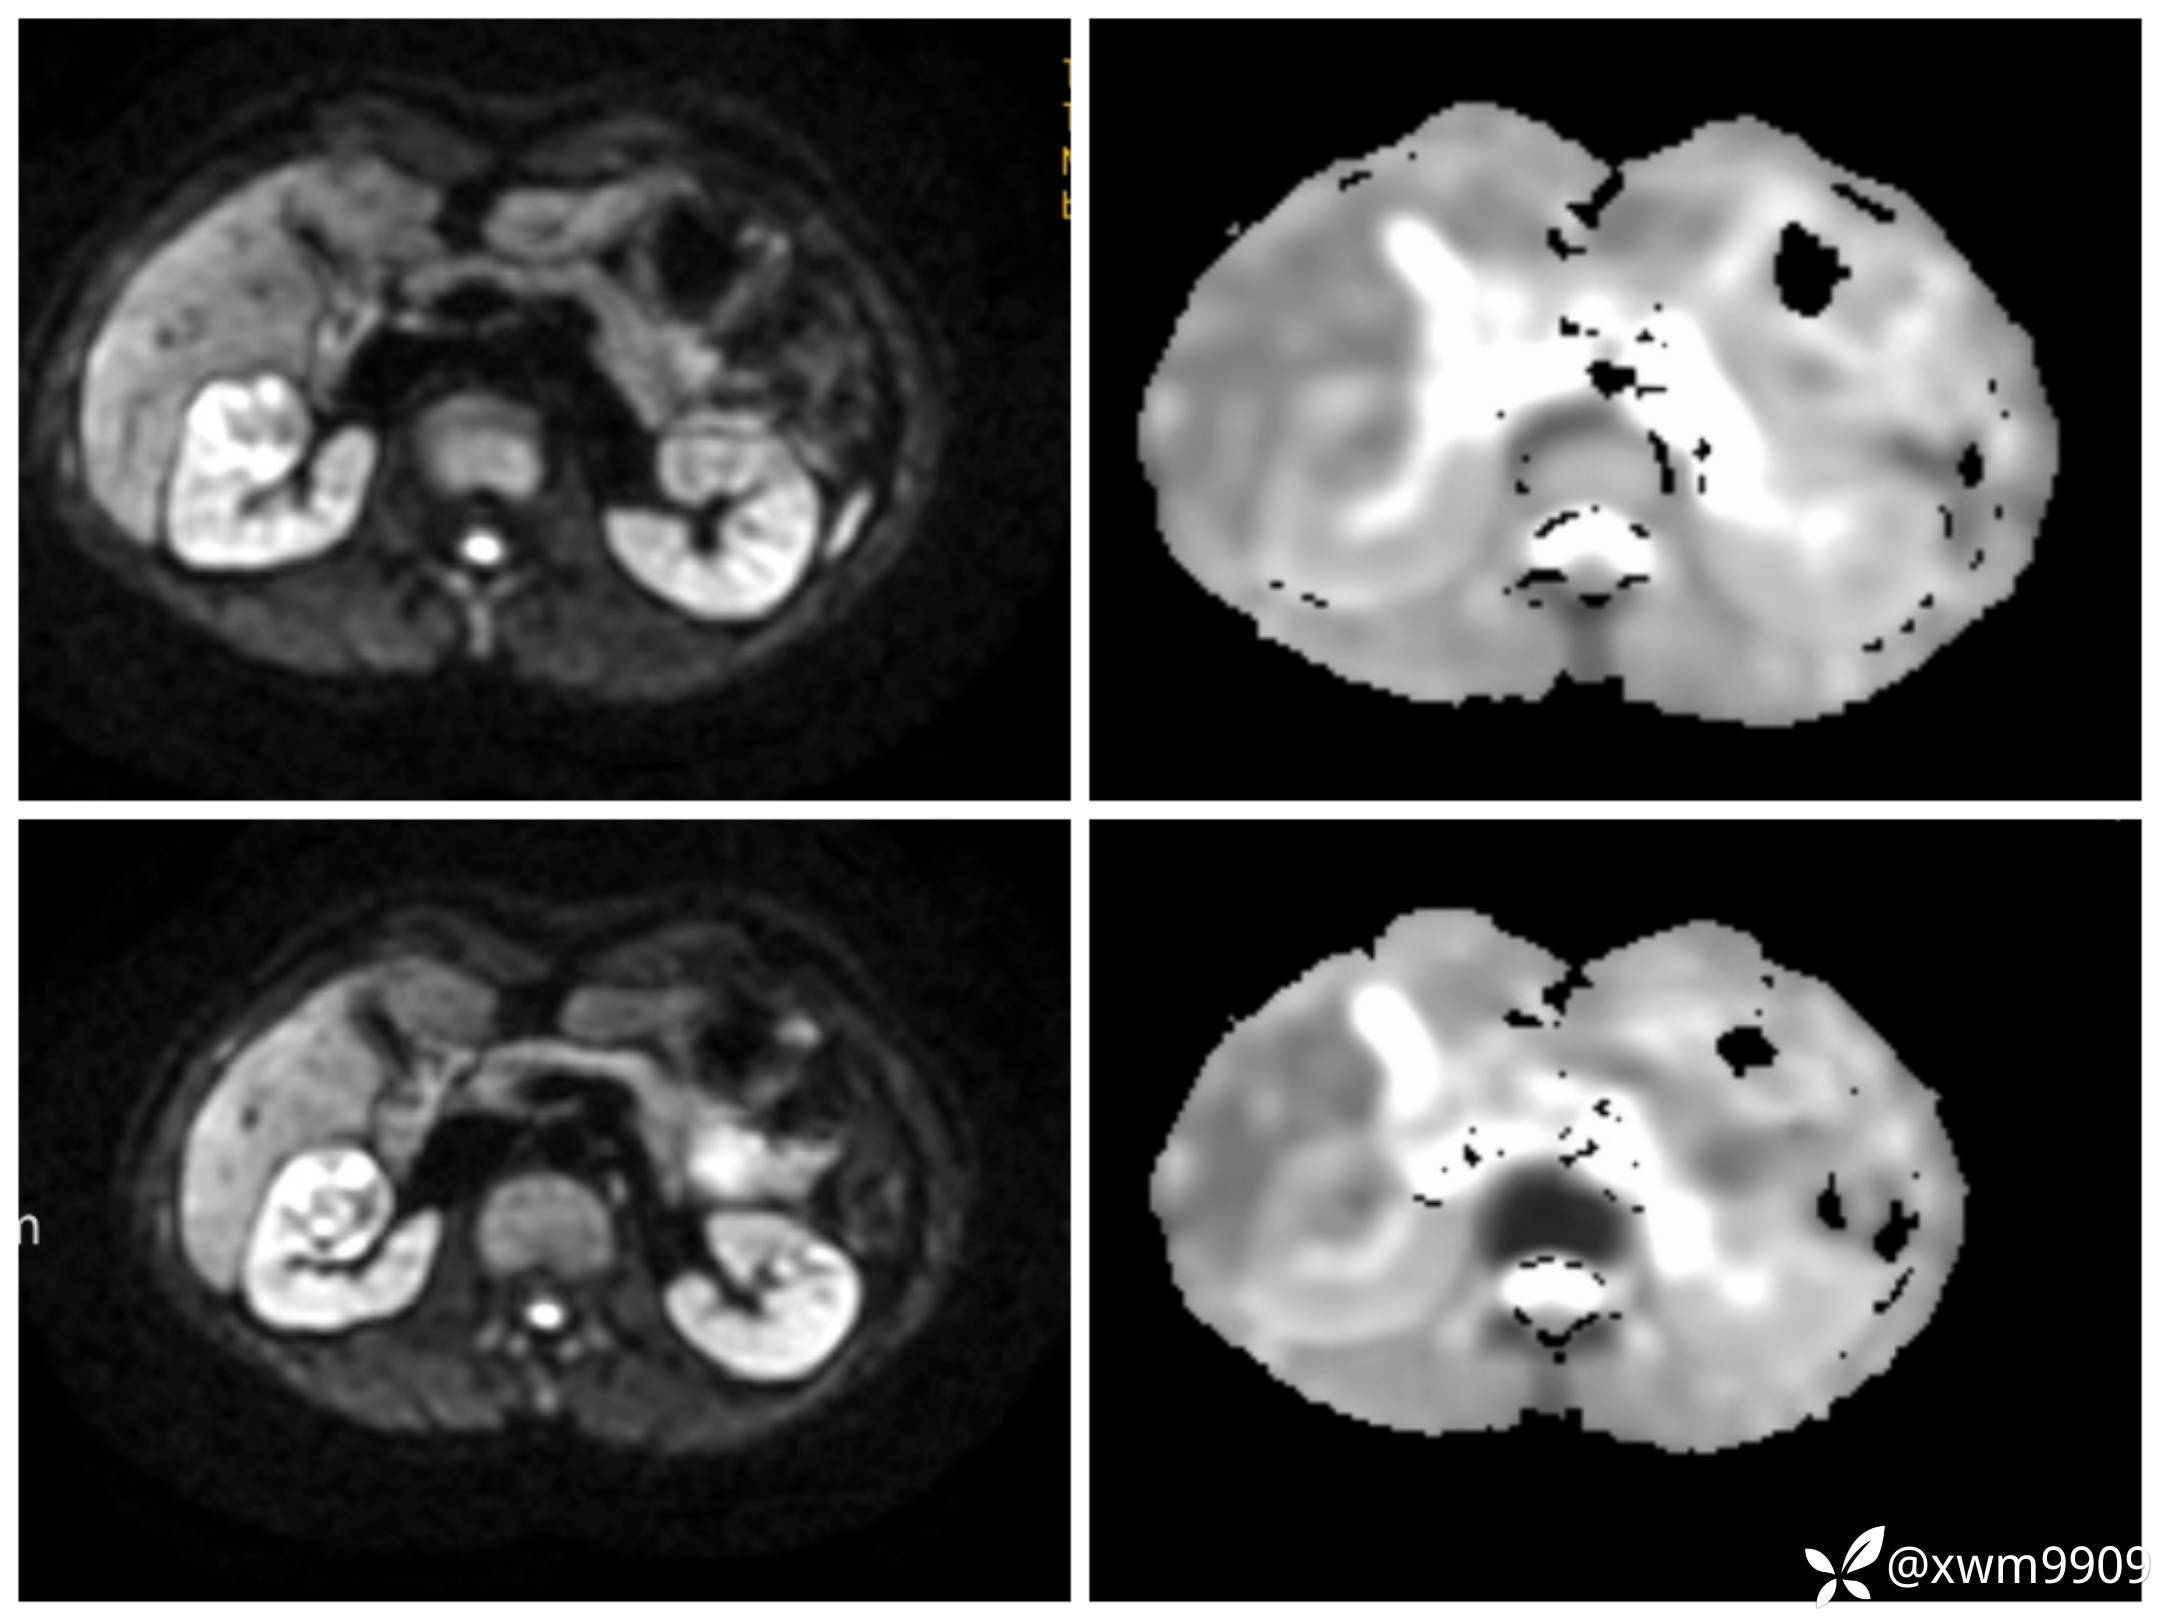

DwI丶ADC: